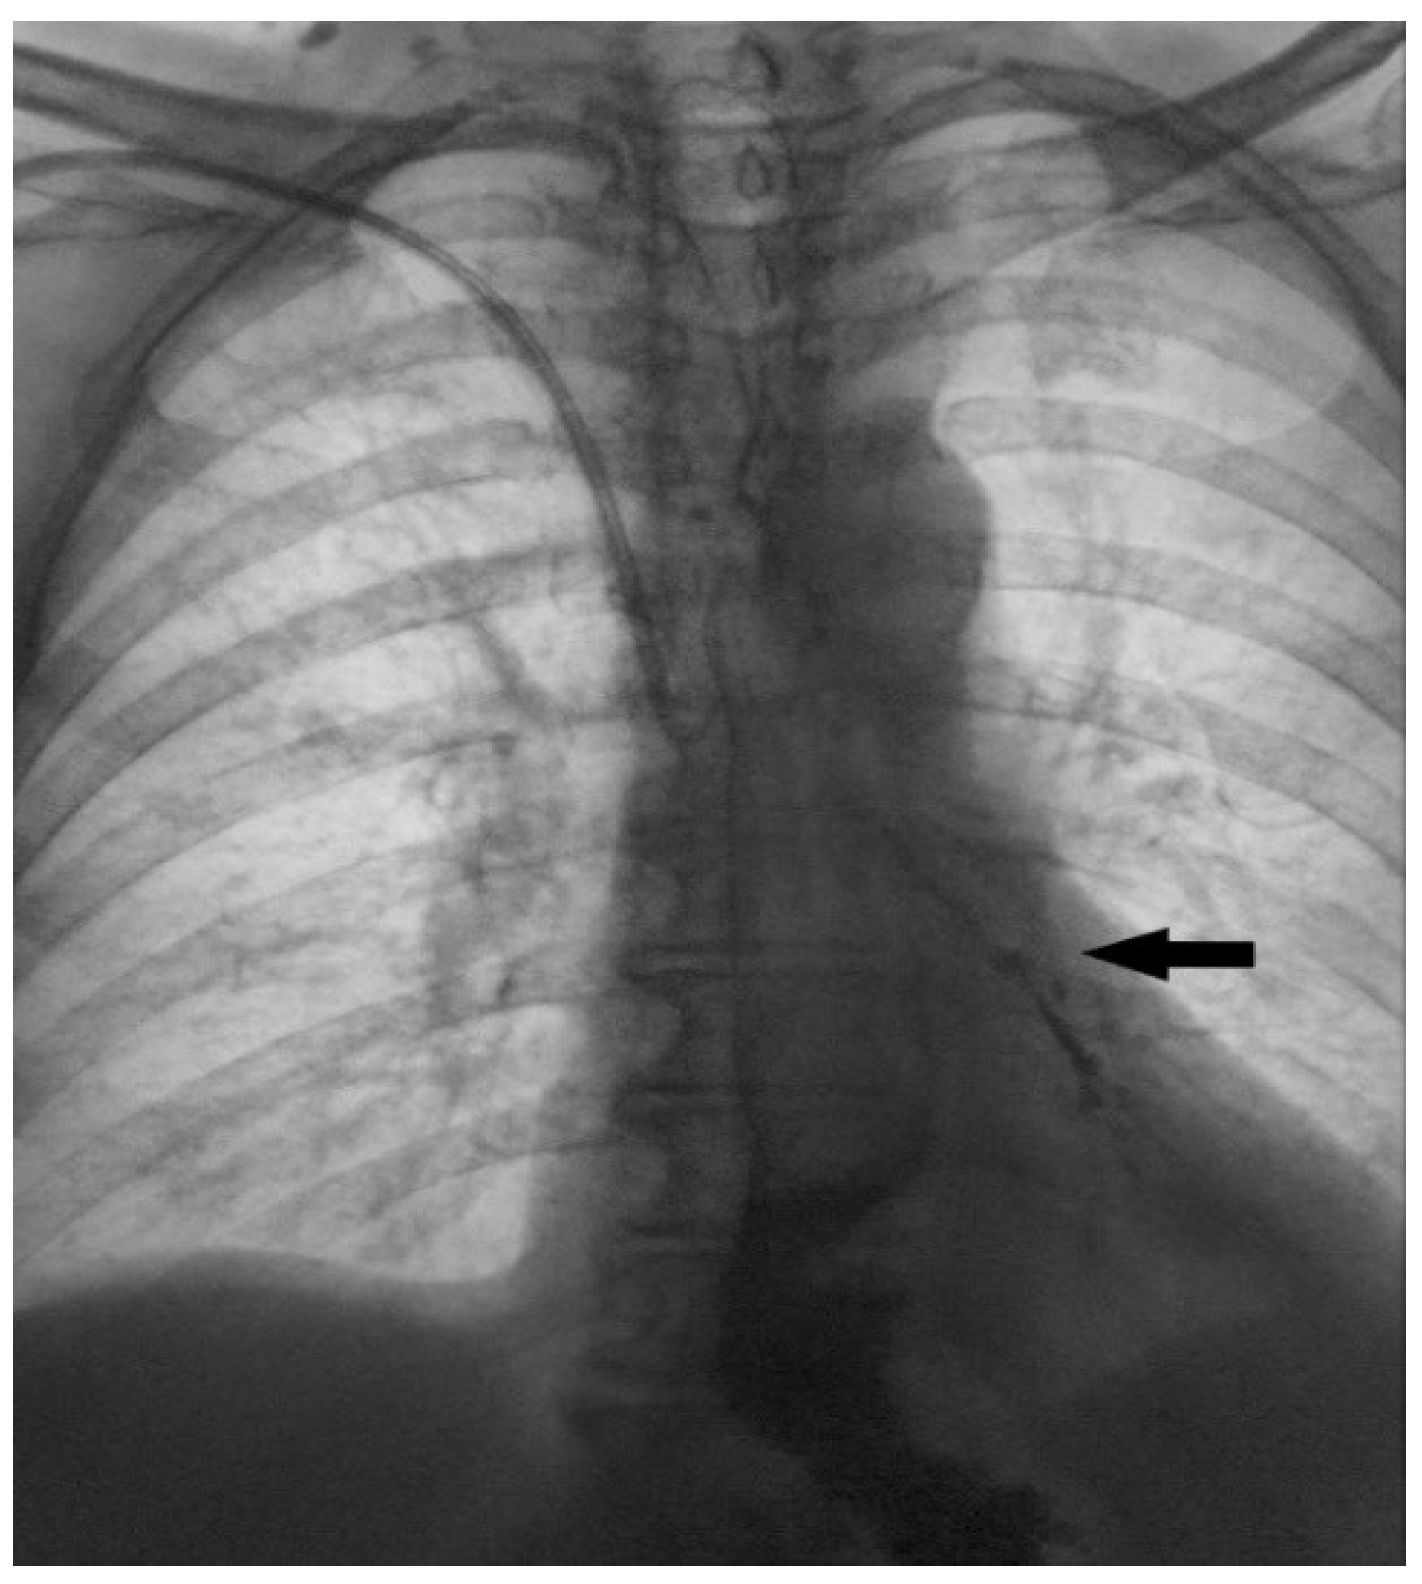

Figure 4. Contrast radiography is a very useful method in terms of establishing this diagnosis. The appearance of contrast in the lumen of the tracheobronchial tree (black arrow) is a direct sign of the fistulization of these structures within the esophagus. This image shows a clear esophagobronchial leak (fistula), which initiated a pronounced cough during the patient’s examination. Tracheobronchoscopy was also performed, showing an opening on the left side of tracheal bifurcation. In the further course of treatment, percutaneous endoscopic gastrostomy (PEG) was performed, and feeding via PEG was initiated. The patient responded well to antibiotics treatment, and was extubated 7 days after the admission to the intensive care unit. Surgery usually represents the primary treatment modality for acquired TEF. However, when surgery is contraindicated or cannot be performed as a primary solution, non-surgical treatment options may be explored. These can serve as a bridge to definitive surgical repair or, in cases of smaller fistulas, may even offer a definitive therapeutic option [3]. Esophageal stenting is an attractive, minimally invasive approach, used in treating predominantly malignant TEFs but also benign etiology [4]. Studies show a great decrease in respiratory complications, length of hospital stay, and overall quality of life, as well as better performance rate in these patients [5,6]. A retrospective study, comparing 22 patients with benign TEF treated with esophageal stenting showed successful closure of the fistula, obtained in 45% of cases. However, if the fistula is located in the proximal third of the esophagus, stenting may not be feasible [7]. Other authors utilize esophageal stenting together with airway stenting. This kind of approach may be more effective than esophageal stenting alone; however, the friction between the two stents can often damage the tissue between the trachea and esophagus. As a result, this combined approach is reserved only in selected cases [8]. After stabilizing the patient’s general condition and conducting a detailed case analysis, experts in this field decided to use a minimally invasive treatment option provided by interventional vascular radiology and attempt to close the fistulous tract by placing an IMPEDE Embolization plug coil to seal the opening in the wall of the esophagus and the trachea. In consultation with the interventional radiologist, the procedure was precisely planned. First, a flexible endoscope was introduced into the esophagus and a guidewire was placed from the lumen of the esophagus into the fistulous tract and a bronchoscope was used to confirm that the end of the guidewire was in the lumen of the trachea. Then, two IMPEDE Embolization plugs were successively placed one on top of the other, to fill the fistulous canal.